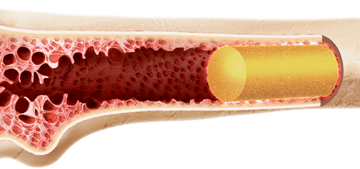

Faixa etária para transplante de medula em casos de doença falciforme é ampliada

Pessoas com mais de 16 anos diagnosticadas com doença falciforme podem, a partir de agora, ser submetidas a um transplante aparentado de medula Pessoas com mais de 16 anos diagnosticadas com doença falciforme podem, a partir de agora, ser submetidas a um transplante aparentado de medula (quando as células provêm de um doador da família). […]